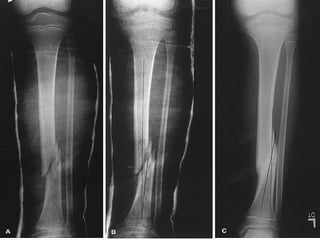

LOCALIZACION Diafisiaria Metafisiaria Epifisiaria Intraarticular Fractura-luxación

EXTENSION Completa Incompleta (fisuras, abombamiento y tallo verde

TIPO DE TRAZO

RELACION DE LOS FRAGMENTOS ENTRE SI Sin desplazamiento Con desplazamiento: lateral, angulada, rotación, diastasado, cabalgado, impactada

LOCALIZACION Diafisiaria MetafisiariaEpifisiaria Intraarticular Fractura-luxación

EXTENSION Completa Incompleta(fisuras, abombamiento y tallo verde

RELACION DE LOSFRAGMENTOS ENTRE SI Sin desplazamiento Con desplazamiento: lateral, angulada, rotación, diastasado, cabalgado, impactada